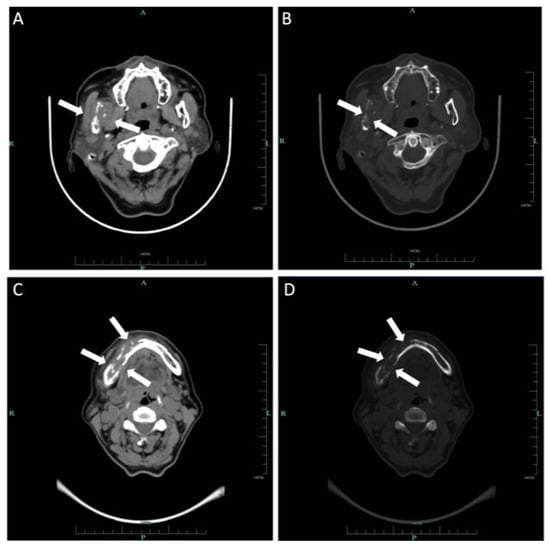

2.2. Case 2